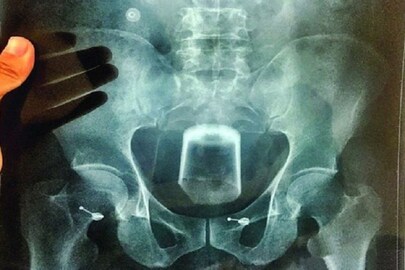

#কলকাতা: নিছক ফেসবুকে আলাপের জেরে বন্ধুত্ব করার মাসুল দিল যুবক। যৌন সম্পর্কে রাজি না হওয়ায় যুবকের মলদ্বারে কাঠের টুকরো ঢুকিয়ে দেওয়ার অভিযোগ ফেসবুক ফ্রেন্ডের বিরুদ্ধে ৷ দক্ষিণ ২৪ পরগনার মগরাহাটের সঞ্জয় মন্ডলকে হুগলির ব্যান্ডেলে ডেকে পাঠায় ফেসবুকের বন্ধু রিক সরকার।

প্রথমে দেখা করার জন্য ডেকে পাঠিয়ে পরে যৌন সম্পর্ক স্থাপনের প্রস্তাব ৷ তাতে রাজি না হওয়াতে পাশবিক অত্যাচারের শিকার হতে হল যুবককে ৷ অভিযোগ, ব্যান্ডেল স্টেশনের কাছে একটি গলিতে সঞ্জয়কে টেনে নিয়ে যায় ফেসবুকের বন্ধু রিক ৷ তারপর তাকে রাগে মারধর করে রিক৷এতেই শেষ নয়, চুল কেটে, উপড়ে নেওয়া হয় ভুরু৷ রাগে সঞ্জয়ের মলদ্বারে কাঠের টুকরো ঢুকিয়ে দেয় রিক ৷

কোনওক্রমে ঘটনাস্থল থেকে পালিয়ে রক্তাক্ত অবস্থায় নির্যাতিত সঞ্জয় হাসপাতালে গিয়ে পৌঁছায় ৷ সেখান থেকেই খবর পান পরিবারের সদস্যরা ৷ পরে চুঁচুড়া থানায় অভিযোগ দায়ের করে সঞ্জয়ের পরিবার ৷